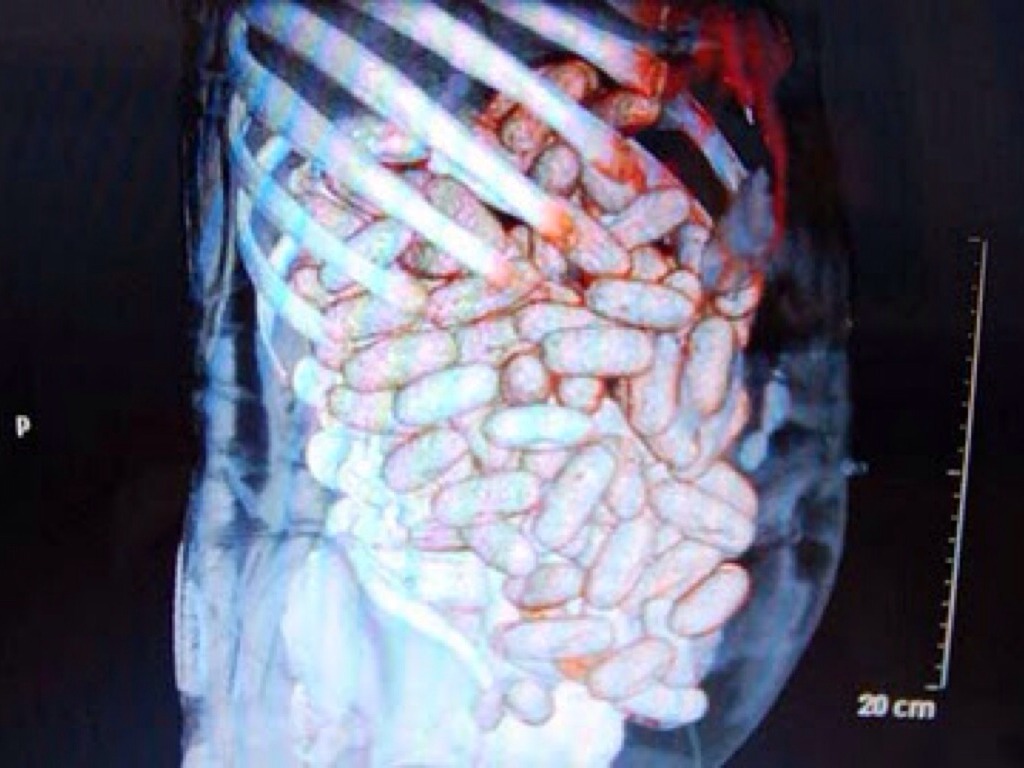

WHAT DID I SWALLOW?

This guy is swallowing a _________?